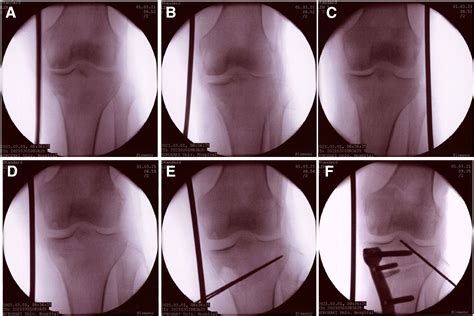

SOLUTION: Anterior tibial curved cortex is a reliable landmark for ...